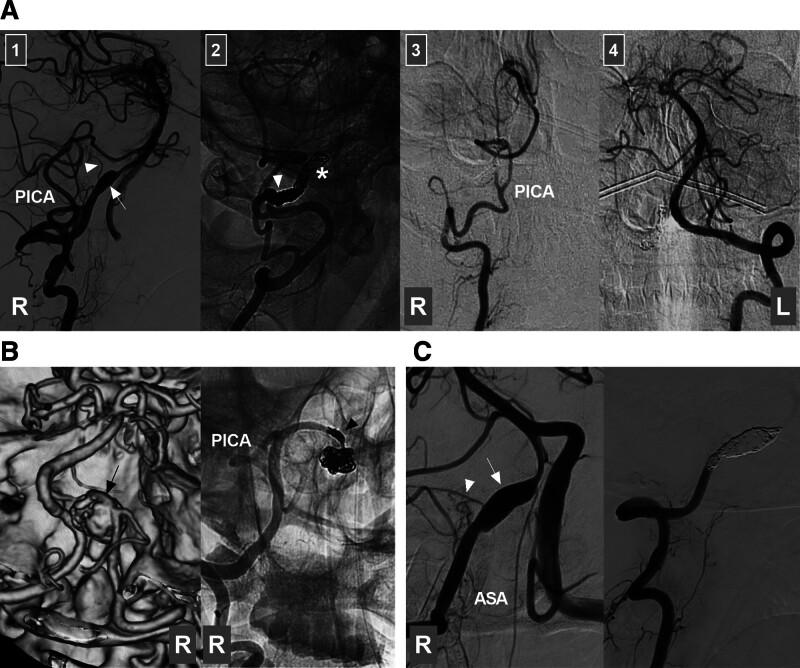

Intracranial vertebral artery (VA) aneurysms are complex entities. Endovascular treatment (EVT) can be used to treat intracranial VA aneurysms. Nevertheless, managing these lesions with EVT remains challenging. Moreover, the suitability of EVT for every type of intracranial VA aneurysm has not been fully confirmed. Therefore, we conducted a needed review of the current literature and our experience summarizing the current status of and advancements in EVT in the management of intracranial VA aneurysms. In our review, several issues are discussed, including the anatomy and anomalies of the intracranial VA, the classification and natural history of intracranial VA aneurysms, indications and techniques for EVT in the management of intracranial VA aneurysms, and the outcomes of and complications experienced by patients who undergo EVT. A flowchart describing EVT options for dissecting intracranial VA aneurysms derived from the findings of this review and our experience is provided. The key to successful EVT is preservation of the posterior inferior cerebellar artery and avoidance of injury to any brainstem perforators. Currently, intracranial VA reconstruction via flow diverter deployment plays an important role in achieving successful treatment. For appropriate cases, both reconstructive and deconstructive EVT can result in good patient outcomes. However, EVT-related complications should be considered. If management of complex intracranial VA aneurysms with EVT would be expected to disproportionally harm the patient, extracranial-intracranial bypass and aneurysmectomy are often necessary. In addition, new products and techniques that show promise for achieving successful EVT in the management of intracranial VA aneurysms are described.